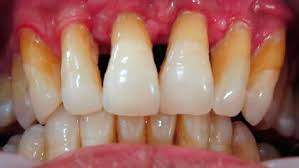

mesa de trabajo 3

Periodontitis

mesa de trabajo 4

Periodontitis Avanzada

En las fases más incipientes de estas enfermedades el tratamiento es un curetaje, con el que se raspa y alisa la raíz del diente y se elimina la placa bacteriana y el sarro de las bolsas periodontales.